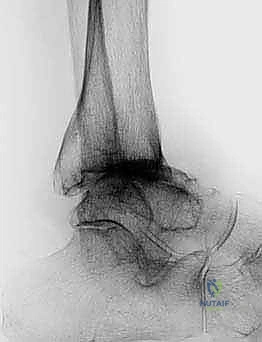

FIG 6 • The TNK ankle replacement for rheumatoid arthritis of the ankle (cemented replacement). A. Preoperative AP view. B. Preoperative lateral view. C. Postoperative AP view 2 years 6 months after the surgery. D. Postoperative lateral view.